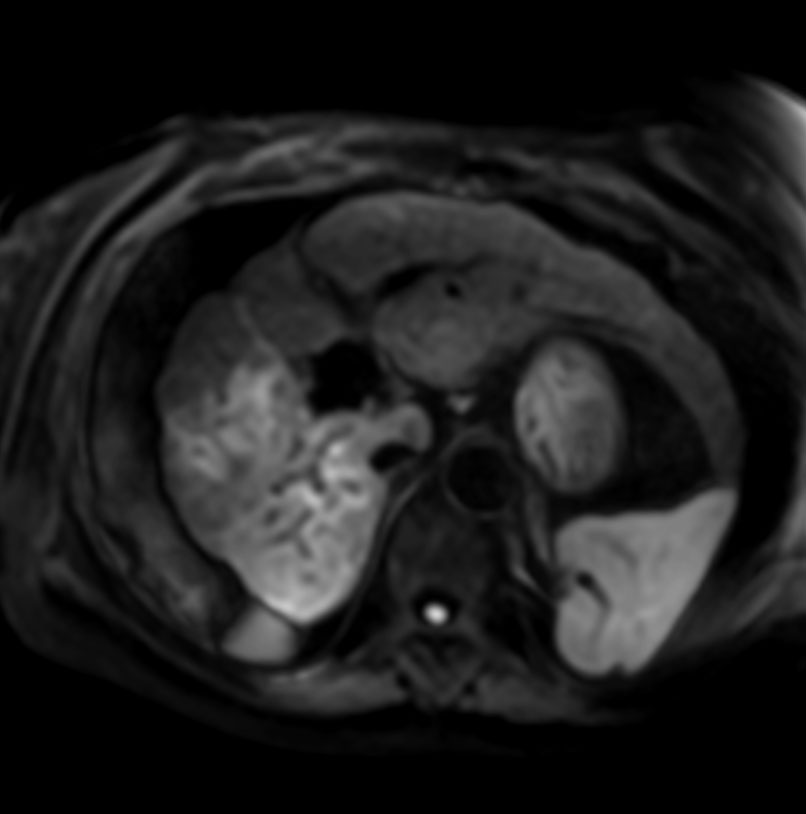

Axial Diffusion - b50